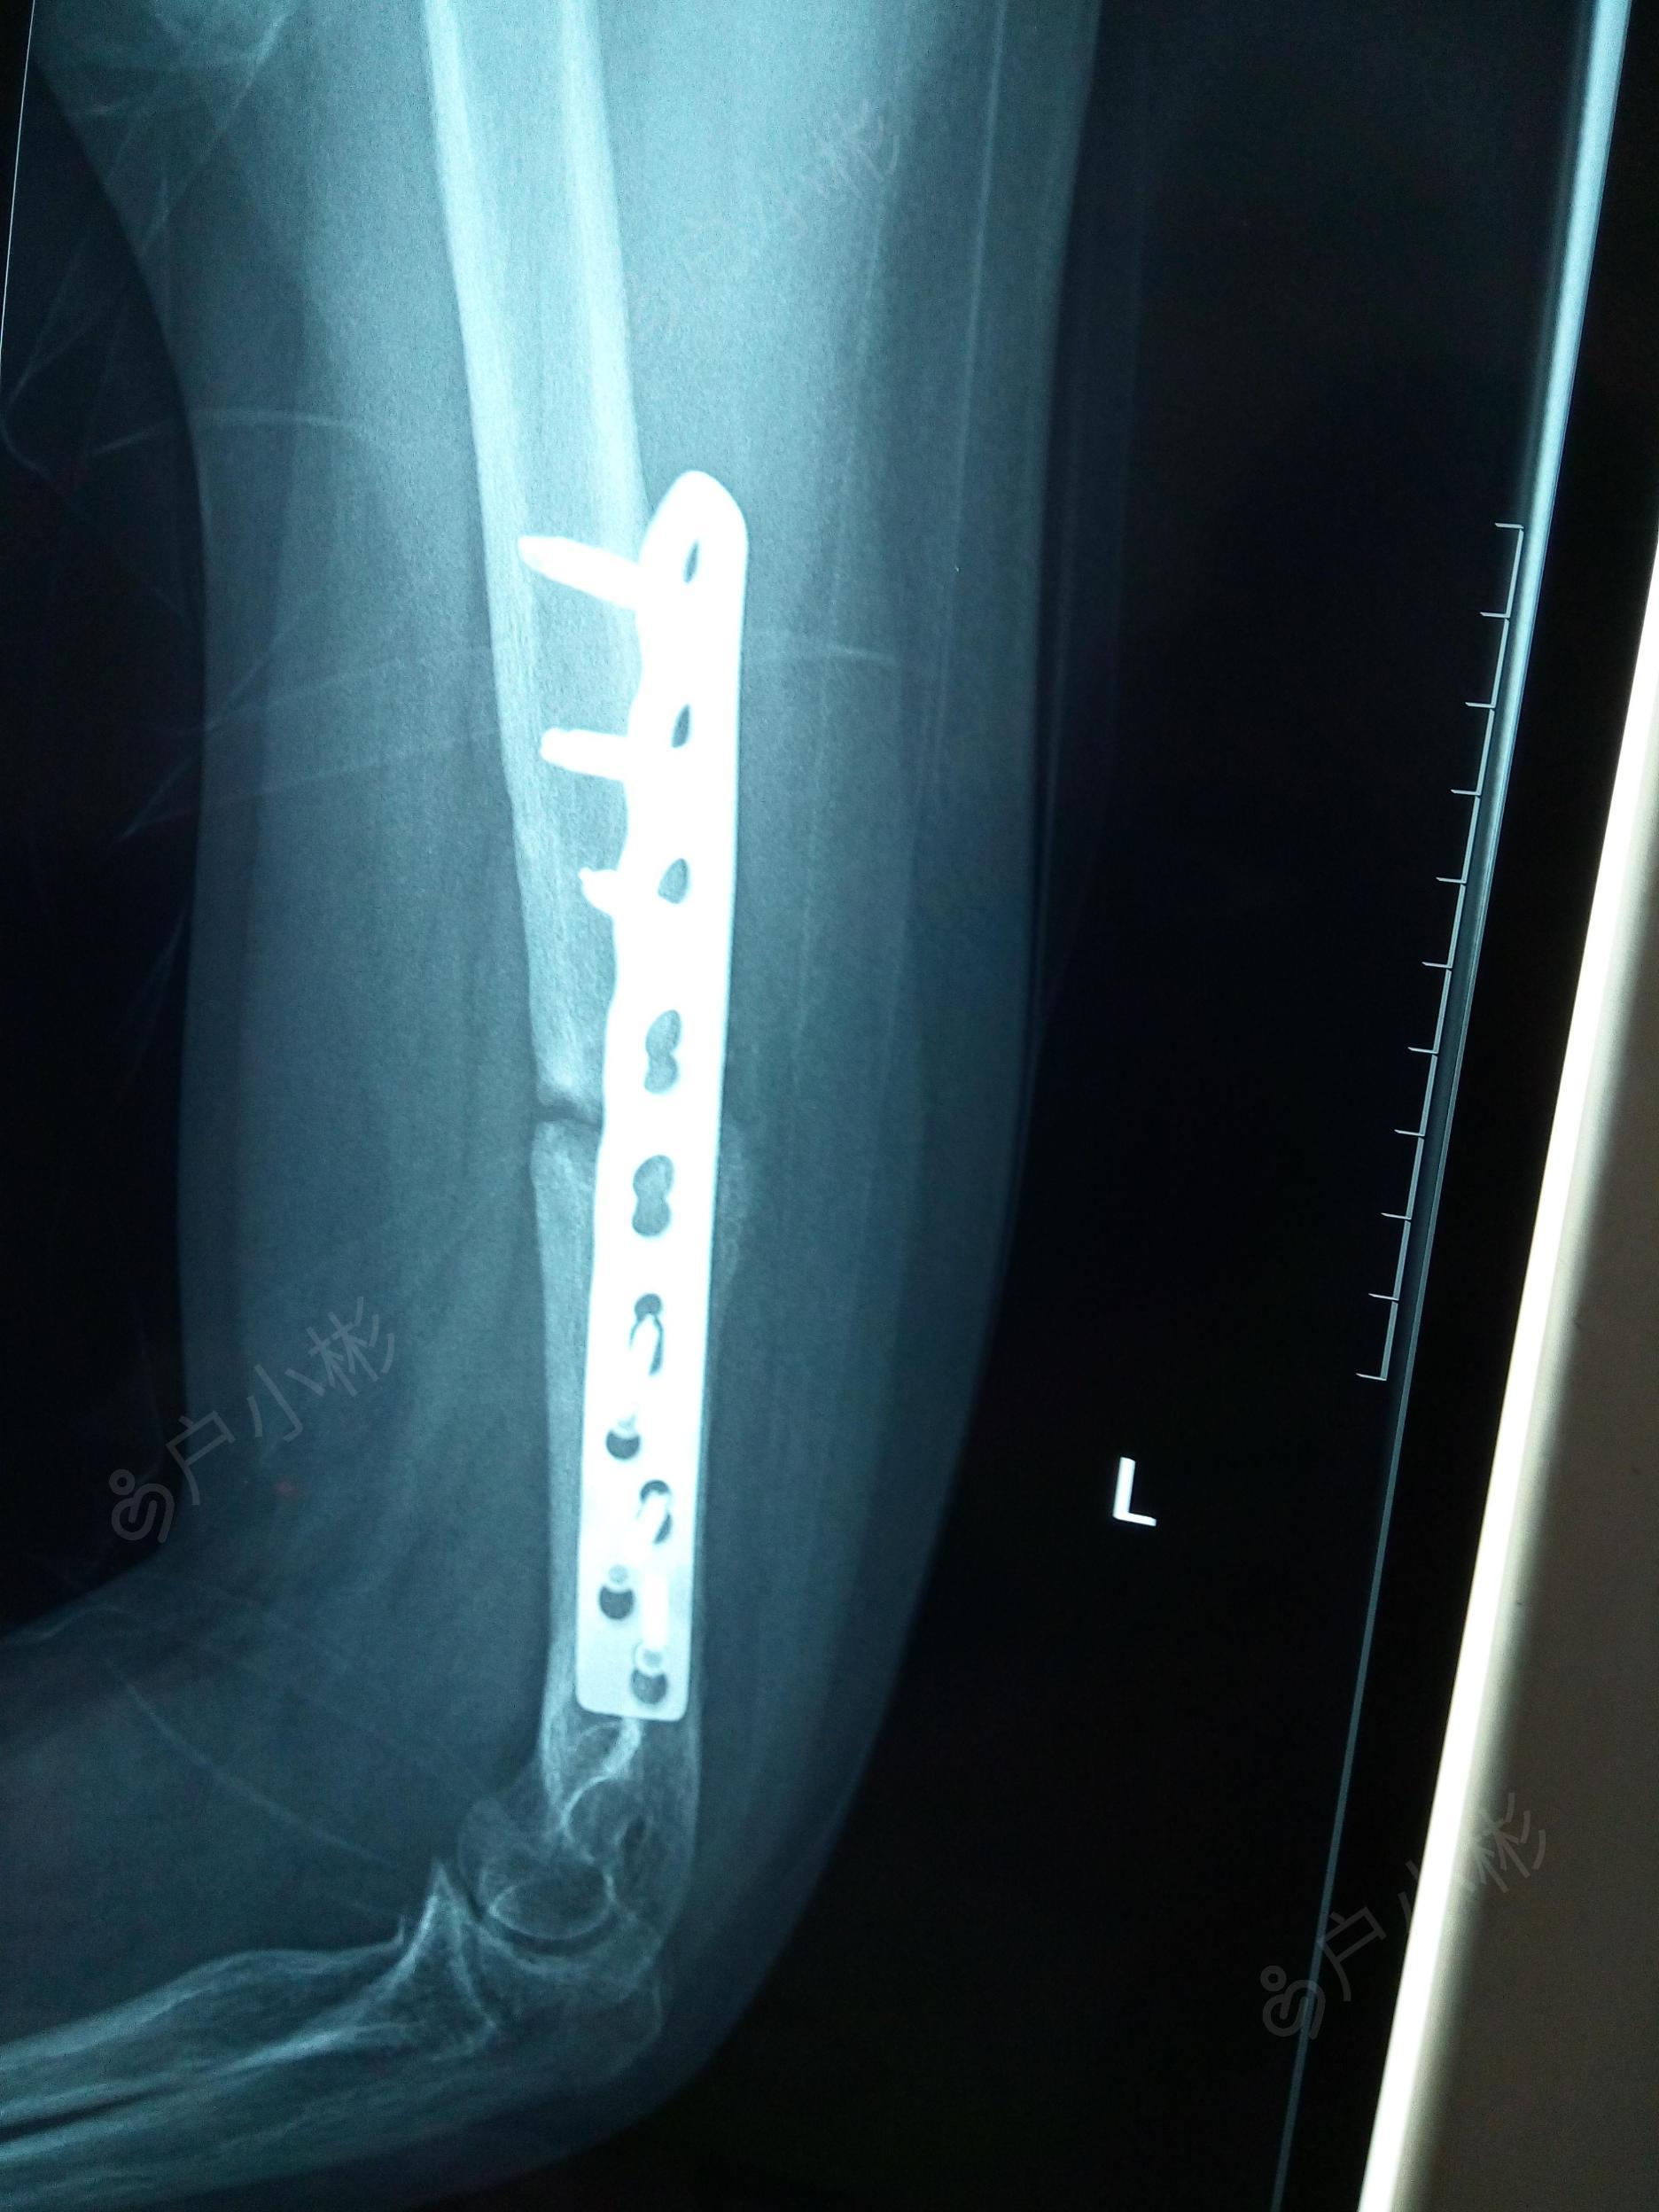

左肱骨干骨折术后半年内固定折断~求下一步治疗方法

图片尺寸1872x2496

锁定钢板固定尺骨骨折.

图片尺寸1840x3264